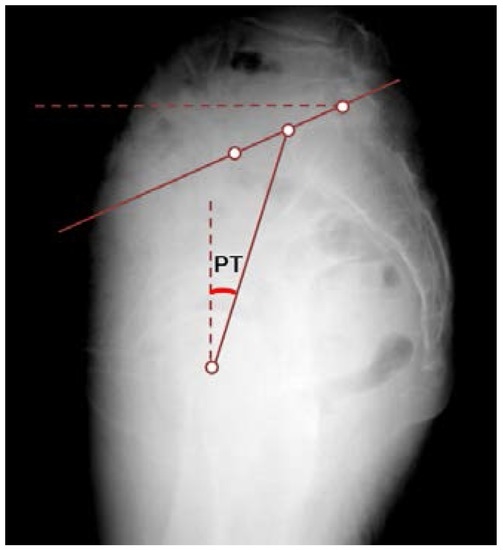

Spine alignment was evaluated on standing true lateral radiographs of the whole spine. The thoracic kyphosis angle (TK), LL, and PT were measured for each subject (Figure 1 and Figure 2). The TK was defined as the angle between the superior endplate of T1 and the inferior endplate of T12. LL was the angle between the inferior endplate of T12 and the superior endplate of S1. PT was the angle between the line connecting the midpoint of the superior endplate of S1 with the center of the femoral head and the vertical line.

Figure 2. Method of measuring pelvic alignment. Pelvic tilt angle (PT) is measured as the line drawn from the center of the superior endplate of S1 to the femoral head.